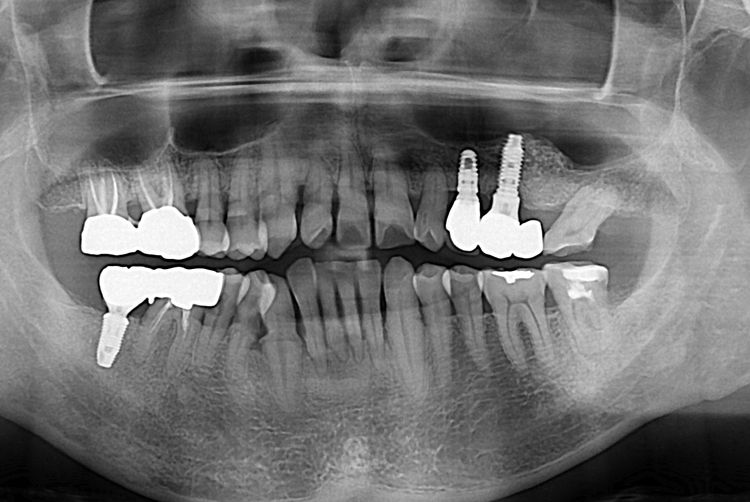

[임플란트] 어금니 임플란트

치료후 : 2019-08-10

세종치과는 많은 환자와 다양한 케이스를 바탕으로

항상 편안한 임플란트 수술을 제공하고자 노력하고,

오래동안 튼튼히 쓸 수 있는 임플란트 수술을 가장 큰 목표로 삼고 있습니다.